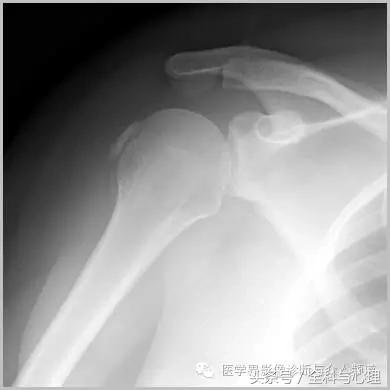

肩关节最常见:肱二头肌长头、肩峰下滑囊钙化,可伴有急性疼痛、肿胀,局部压痛。

肱二头肌肌腱钙化(肩周炎)

肩周炎